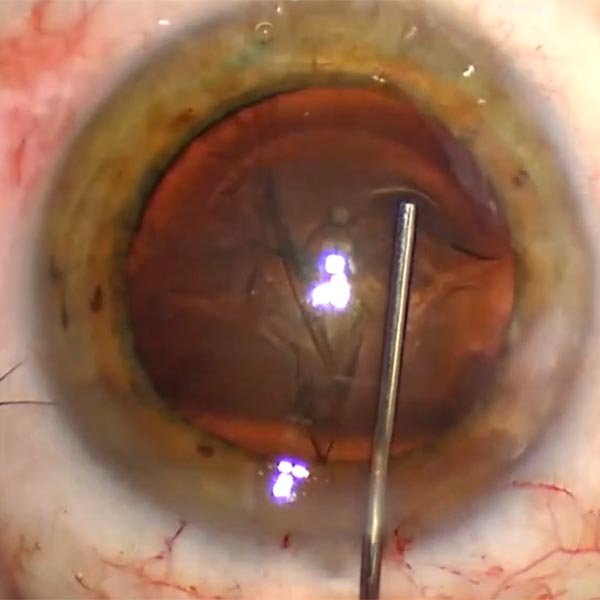

Manejo de una subluxación del cristalino por FLACS

José Gegúndez, Nuria Perales Casado